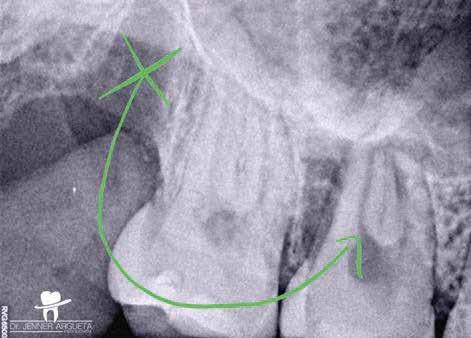

1. a–f ábrák: A cingulumon keresztül gömbfúróval kialakított hozzáférés a trepanációs kavitás labiális irányba történő túlzott mértékű kiterjesztését eredményezheti, és ez lényegesen növelheti a perforáció esélyét (a). A guttapercha átsejlik a lágyrészek alatt (b). Klinikailag igazolt perforáció (c). A preoperatív sagittális irányú CBCT-szeleten jól látható a labiális perforáció (d). Labiális irányú perforáció (fekete nyíl; e). A tényleges gyökércsatorna (piros nyíl; f).

2. a-b ábrák: A cingulumon keresztül gömbfúróval végzett trepanálás túlzott pericervikális dentin áldozattal, fordított tölcsér effektussal és perforációk kialakulásával járhat (fehér nyíl).

A frontfogakban történő hozzáférési nyílás kialakítása

A frontfogakban a hozzáférési nyílás kialakítását hagyományosan a fogak linguális vagy palatinális felszínén, a cingulumon keresztül egy gömbfúró segítségével kezdjük. A linguálisan elhelyezkedő kiemelkedés teljes eltávolítása, továbbá a pulpaszarvak teljes feltárása egy háromszög alakú hozzáférési nyílást eredményez. 7 Ezt a módszert a fogak esztétikai megjelenésének megőrzése érdekében fejlesztették ki. Ez azonban időnként a saját foganyag indokolatlan eltávolításával, a trepanációs kavitás labiális irányba történő túlzott kiterjesztésével, perforációval, valamint a fog kritikus helyen, a pericervikális dentin (PCD) területén történő meggyengítésével jár (1. a–f és 2. a-b ábrák). 19 Felmerült, hogy a pericervikális dentin rendkívül fontos szerepet játszik a rágóerő gyökerek irányába történő továbbításában, és elképzelhető, hogy a gyökérkezelt fogak hosszú távú megtartása szempontjából a legfontosabb tényező az ép pericervikális dentin megőrzése lehet. 20 A cingulumon keresztül történő hozzáférési nyílás

kialakítása során fennáll a fog labiális irányú perforációjának veszélye, mivel ilyenkor a foganyag elvételét labiális irányú fúrótartással kezdjük. Nemrégiben újragondolták a